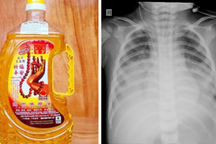

Bệnh viện Nhi Hà Nội vừa tiếp nhận trường hợp trẻ nam cấp cứu vì uống phải tinh dầu đuổi muỗi (Ảnh: Bệnh viện cung cấp).

Bệnh nhi tổn thương phổi rất xấu và lan tỏa cả hai bên. Phim chụp phổi cho thấy tổn thương rất nặng, có thể gây suy hô hấp cấp tính và tiềm ẩn nguy cơ xơ phổi nặng nề về sau. Trẻ đã có nhiều cơn co giật trước khi được chuyển đến bệnh viện.